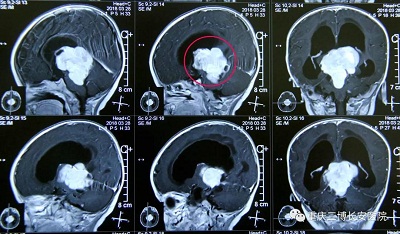

CT:标注处为肿瘤

辅助检查:外院头颅CT提示三脑室占位,性质待查;我院行头颅MRI检查提示三脑室占位,考虑畸胎瘤?生殖细胞瘤?

MRI:标注处为肿瘤

根据小鱼儿的病史、临床表现、查体及辅助检查,初步诊断为三脑室占位性病变(畸胎瘤?生殖细胞瘤?)

术中探查见:肿瘤约6cmX5cm大小,质地不均,大部分质地坚韧,肿瘤血运丰富,边界清,肿瘤下方突入四脑室。

术后CT:肿瘤切除完全